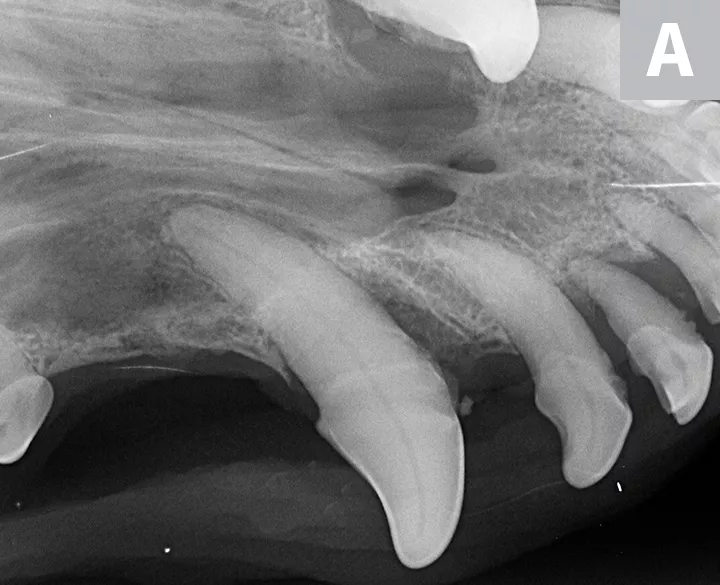

Figure 2

Dental radiographs of the right (A) and left (B) maxillary canine teeth (lateral views) and the rostral maxillae (C; occlusal view) confirmed mild horizontal and severe vertical bone loss at the mesial aspect of both maxillary canine teeth. Moderate to severe horizontal bone loss at the right maxillary first incisor tooth (blue arrow) and total loss of attachment with inflammatory root resorption at the right maxillary second incisor tooth (yellow arrow) were present. The remaining maxillary incisor teeth were affected by mild horizontal bone loss. Although the occlusal view of the rostral maxillae is slightly asymmetric, osteolysis was evident in the area of the left palatine fissure (red arrow). Mild horizontal bone loss was diagnosed at several other teeth. In addition, retained root tip of the left maxillary (presumably) first premolar tooth (white arrow) was identified.